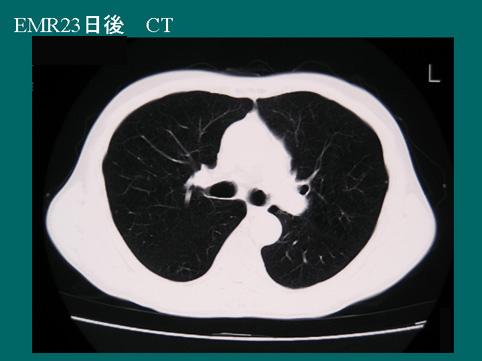

A case of superficial IIc type esophageal cancer which was removed by an endoscopic mucosal resection associated with mediastinal emphysema and cured by conservative therapy.

CT